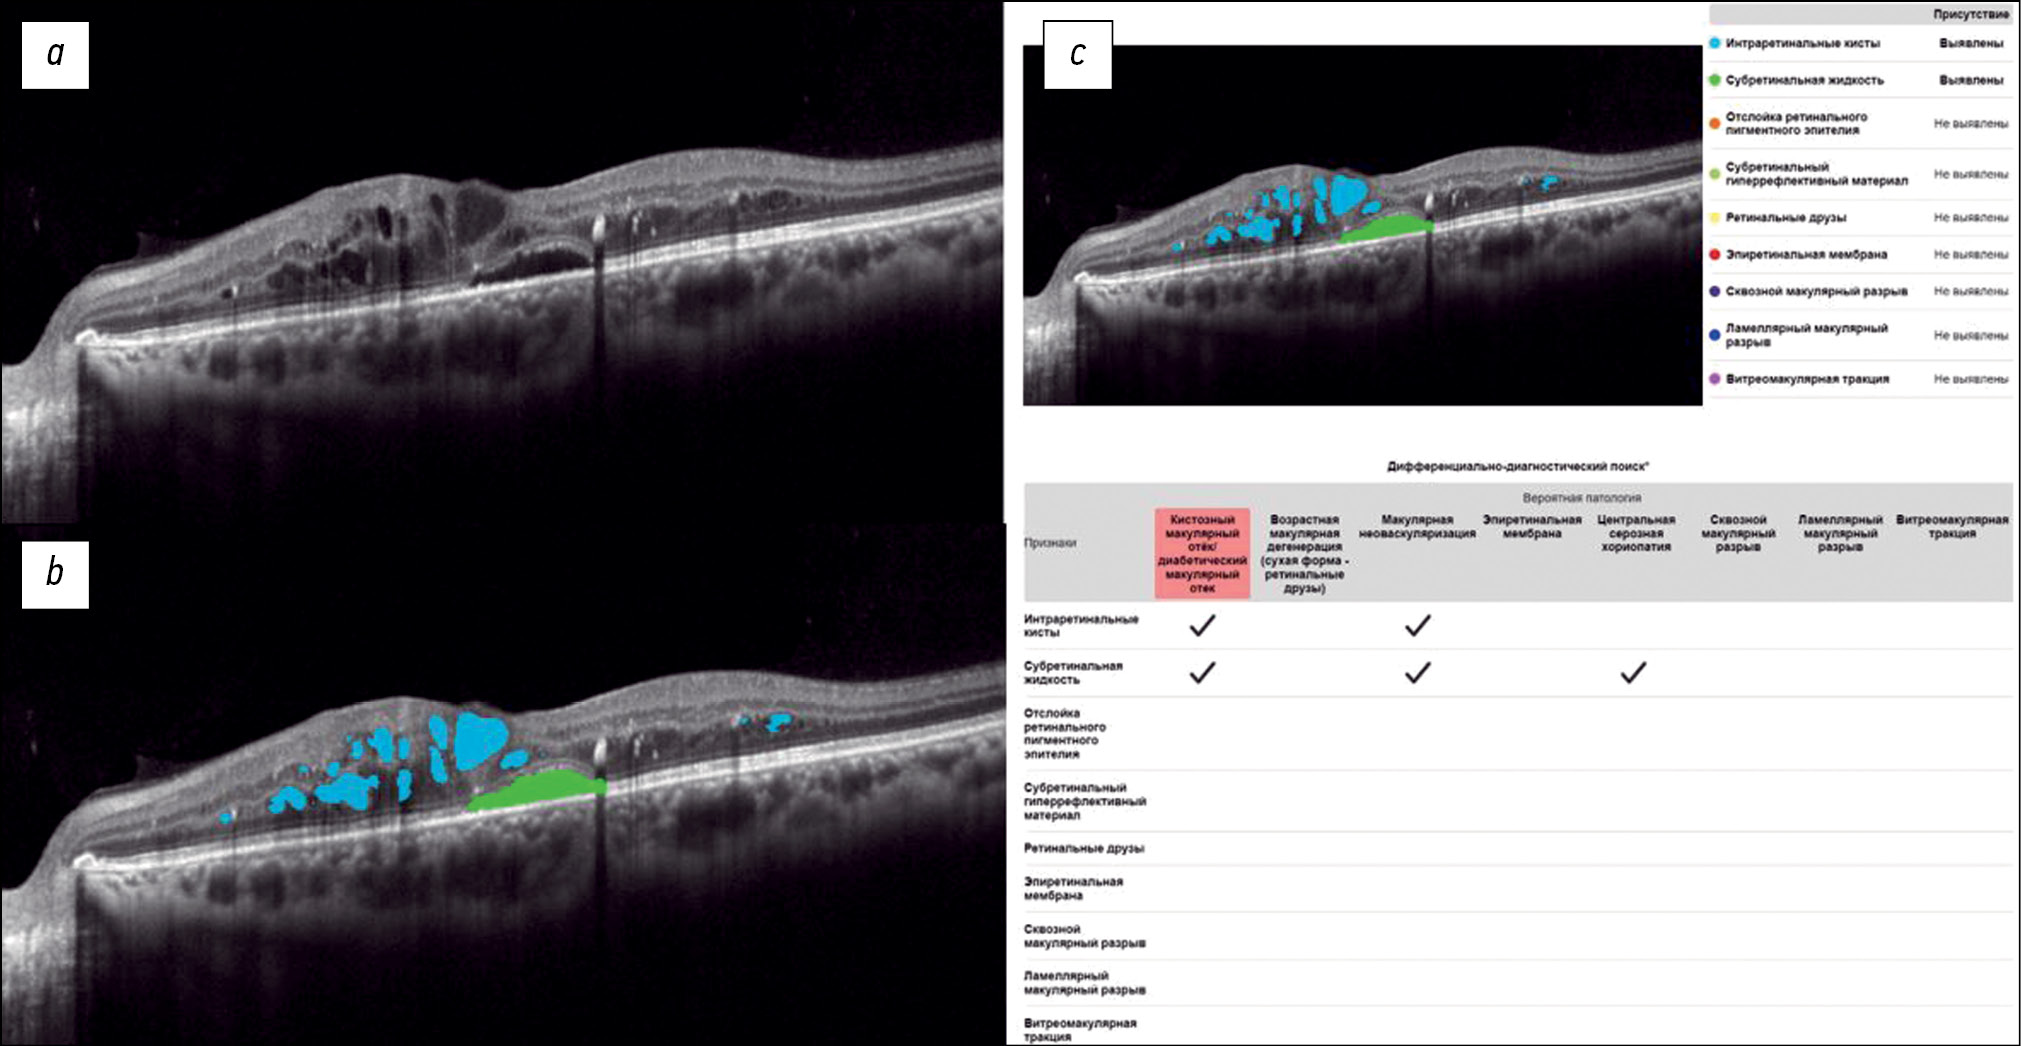

Exploring the possibilities of an artificial intelligence program in the diagnosis of macular diseases

BACKGROUND: Macular diseases are a large group of pathological conditions that cause vision loss and visual impairment. Early diagnosis of such changes plays an important role in treatment selection and is one of the crucial factors in predicting outcomes.

AIM: To examine the potential of an artificial intelligence program in the diagnosis of macular diseases using structural optical coherence tomography scans.

MATERIALS AND METHODS: The study included patients examined and treated at the Federal Research and Clinical Center of Specialized Medical Care and Medical Technologies and Moscow Regional Research and Clinical Institute. In total, 200 eyes with macular diseases were examined, as well as eyes without macular pathologies. A comparative clinical analysis of structural optical coherence tomography scans obtained using an RTVue XR 110-2 tomograph was conducted. The Retina.AI software was used to analyze optical coherence tomography scans.

RESULTS: In the analysis of optical coherence tomography scans using Retina.AI, various pathological structures of the macula were identified, and a probable pathology was then determined. The results were compared with the diagnoses made by ophthalmologists. The sensitivity, specificity, and accuracy of the method were 95.16%, 97.76%, and 97.38%, respectively.

CONCLUSION: Retina.AI allows ophthalmologists to automatically analyze optical coherence tomography scans and identify various pathological conditions of the fundus.